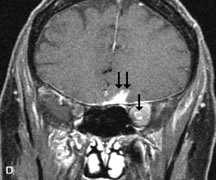

Fig. 22. A and B. T1- and (C) T2-weighted MR scans demonstrate a poorly defined multicompartmental mass enveloping the lateral rectus, superior rectus, and levator palpebrac superioris muscles. The lesion is isointense to brain on T1- and T2-weighted scans, as is typical for highly cellular neoplasms. D. Postcontrast fat-suppressed T1-weighted scan demonstrates intense enhancement of the infiltrating intraconal and extraconal tumor.

Lymphomas have MRI characteristics similar to those of inflammatory lesions in that they are hypointense to fat and isointense to muscle on T1-weighted images (Fig. 22). They may appear hyperintense to fat on T2-weighted images, perhaps owing to less fibrosis than that seen in orbital inflammatory pseudotumor, although this is not a consistent finding.31,50,66 Lymphoid tumors typically enhance moderately after contrast injection. Unfortunately, studies have shown that tumor density and homogeneity are similar between inflammatory and malignant orbital infiltrates, and MRI cannot differentiate these lesions.72,73